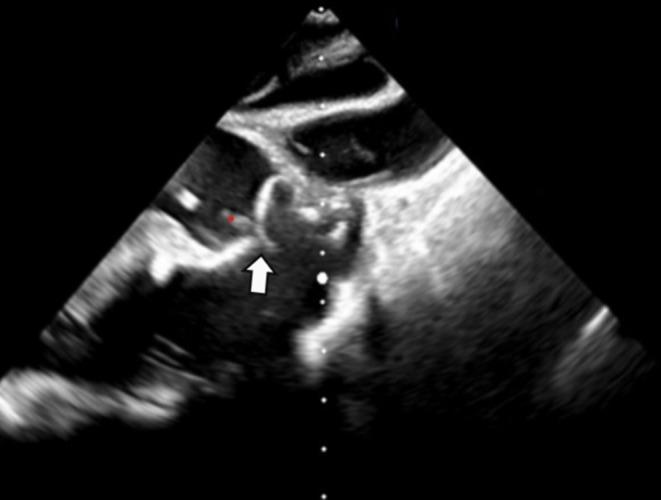

Spontaneous Resolution of Hemolysis After Ventricular Septal Defect Closure With an Amplatzer Device.

A wait and see approach can be maintained in cases with mechanical hemolysis after percutaneous VSD closure, even when the cause is not homogeneous.

对于经皮室间隔缺损封堵术后发生机械性溶血的病例,即使病因并不相同,也可采取观察等待的方法。